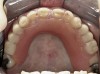

Initial examination revealed a partial edentulous patient with extensive wear of the maxillary anterior teeth and moderate wear in the mandibular teeth (Figure 1, Figure 2, Figure 3, Figure 4, Figure 5, Figure 6 and Figure 7). The patient’s maxillary and mandibular RPDs also showed excessive wear and multiple signs of fractures (Figure 2 and Figure 3). The patient had been wearing a mandibular nightguard for 8 years.

Figure 2  Intraoral occlusal view of maxillary dentition with the existing removable prosthesis presenting excessive signs of wear.

Figure 2

Figure 4  Intraoral occlusal view of maxillary dentition presenting excessive signs of wear.

Figure 4